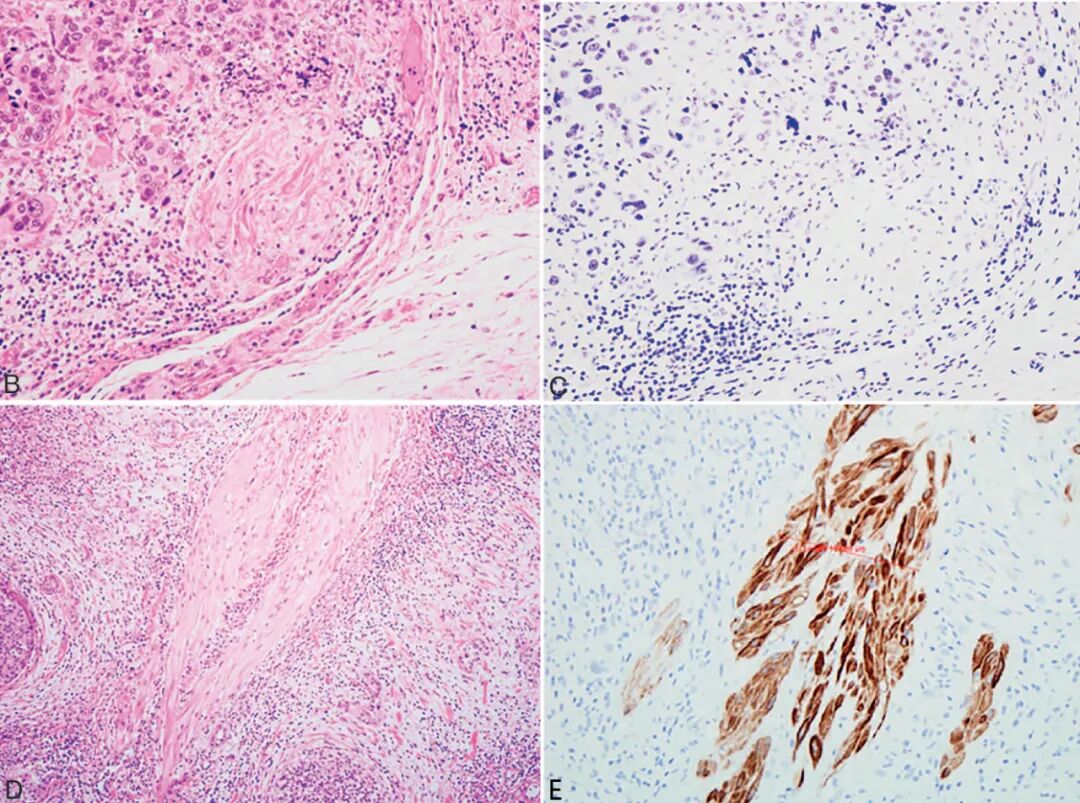

图4B .Smoothelin 在膀胱癌中的应用。尿路上皮癌细胞侵犯平滑肌束;

图4C .Smoothelin 在膀胱癌中的应用。与图8B同一视野,显示Smoothelin微弱着色,提示黏膜肌层被累犯;

图4D .Smoothelin 在膀胱癌中的应用。另一例尿路上皮癌侵犯平滑肌束;

图4E. Smoothelin 在膀胱癌中的应用。与图8D同一视野,显示Smoothelin强阳性,提示固有肌层被累犯。